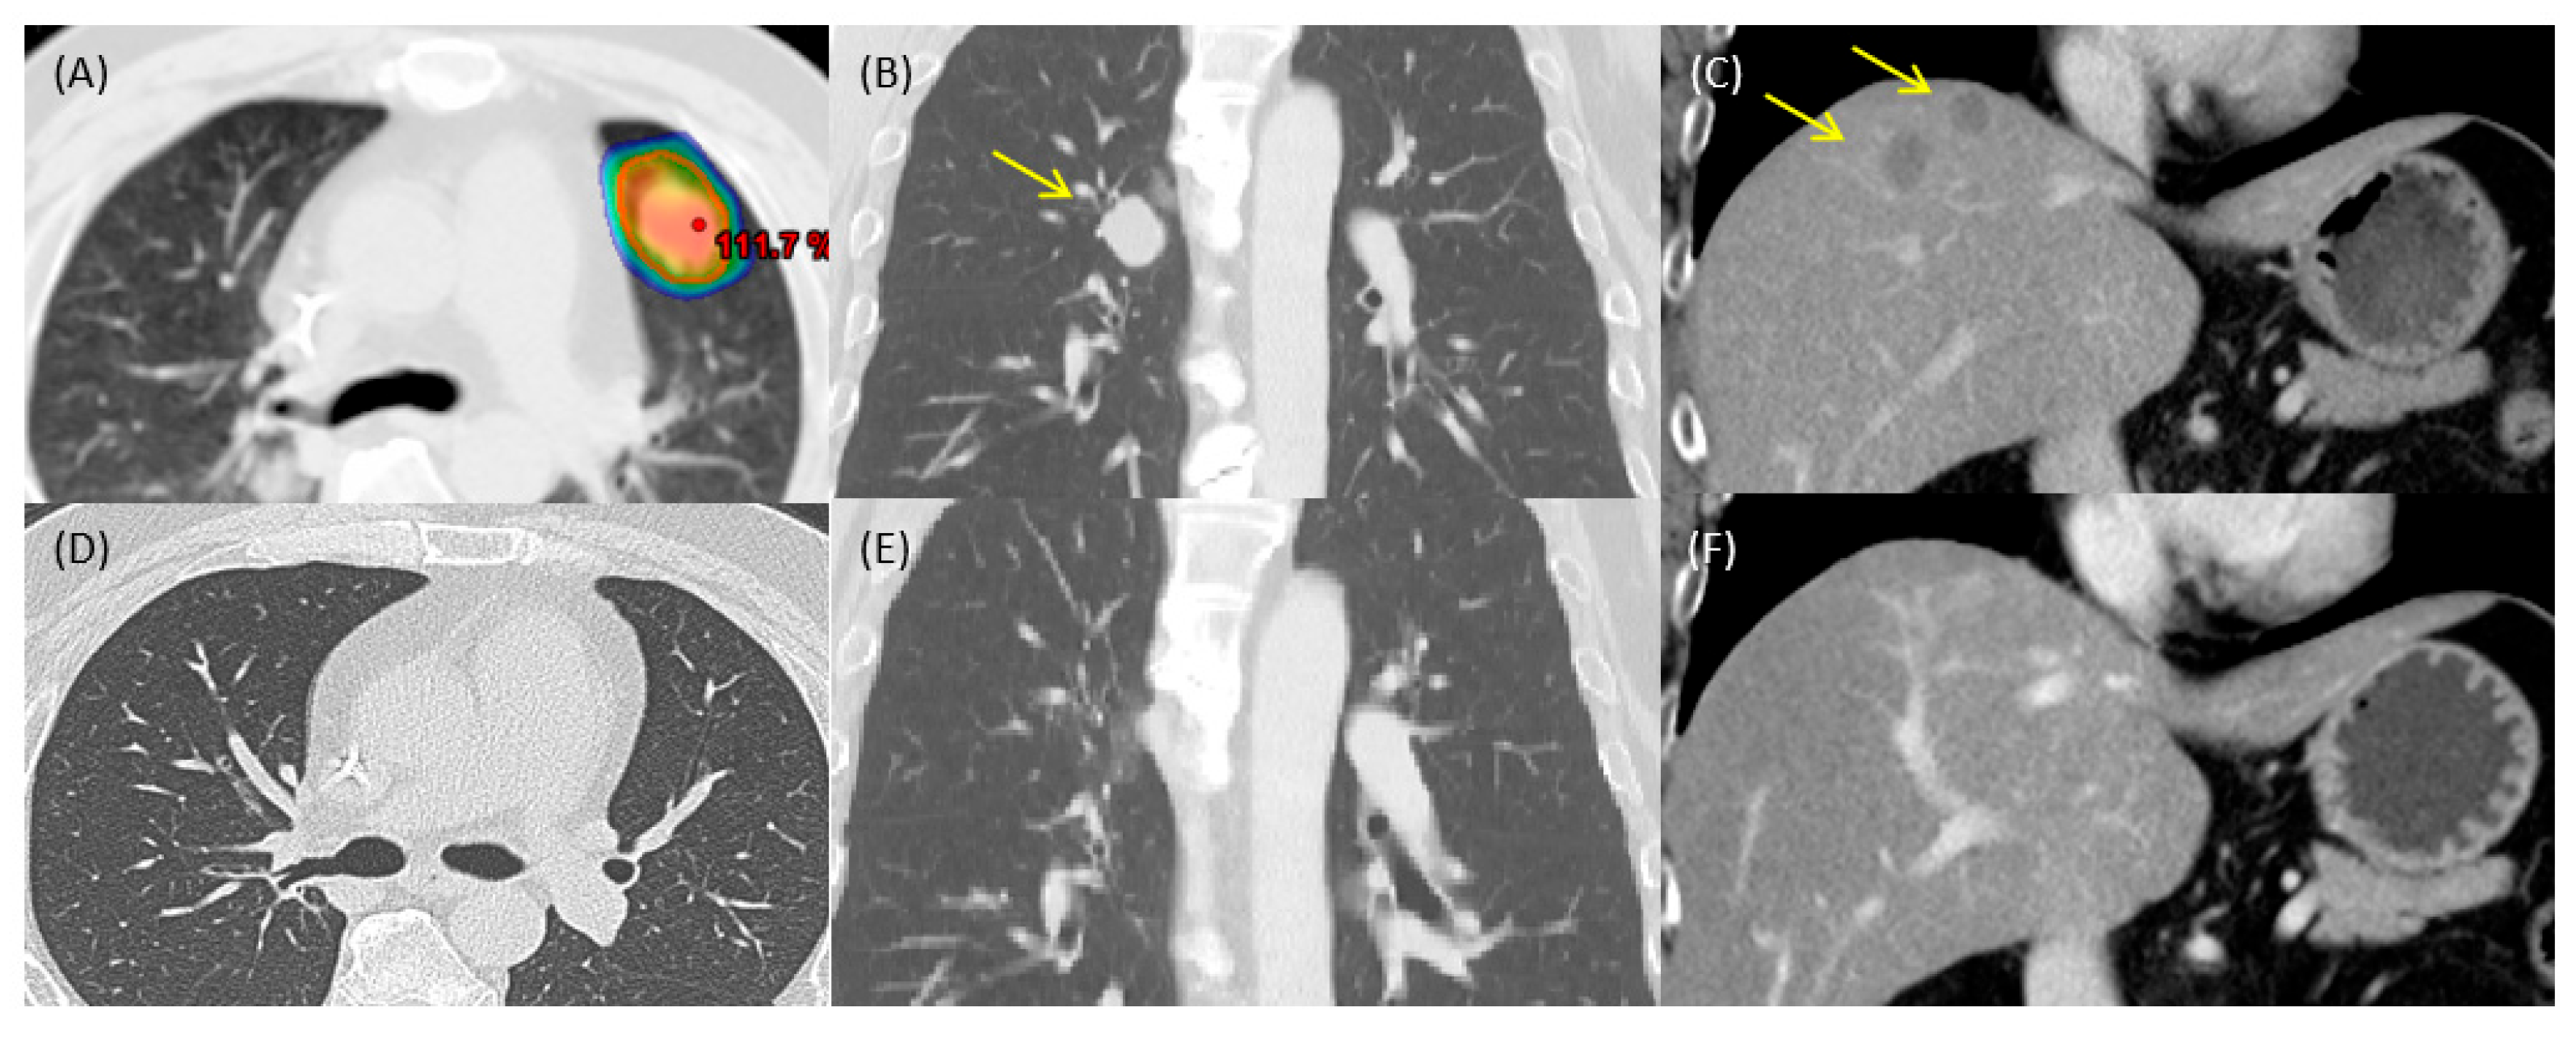

2. Case Report